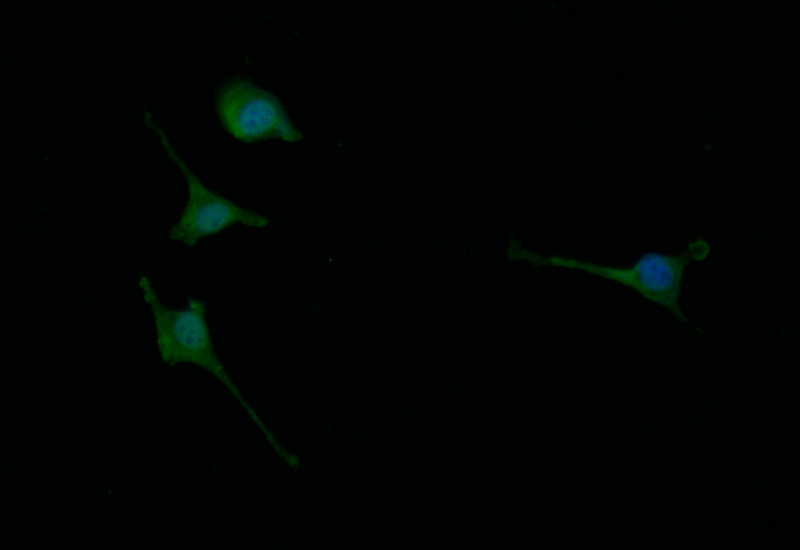

Immunofluorescence staining of SH-SY5Y with CSB-RA825574A0HU at 1:30, counter-stained with DAPI. The cells were fixed in 4% formaldehyde and blocked in 10% normal Goat Serum. The cells were then incubated with the antibody overnight at 4°C. The secondary antibody was Alexa Fluor 498-congugated AffiniPure Goat Anti-Rabbit IgG(H+L).